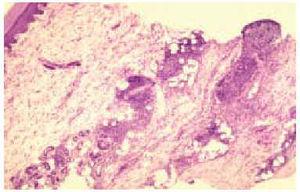

En el estudio histológico de todas las biopsias se observó un infiltrado perivascular en la dermis superficial y profunda compuesto por linfocitos, polimorfonucleares y abundantes eosinófilos (figs. 2 y 3). La intensidad del infiltrado fue variable, siendo muy denso y con un gran número de eosinófilos en los casos 1 y 4, en los que además se observó un marcado edema en la dermis papilar con formación de una ampolla subepidérmica. El resultado del estudio inmunohistoquímico se resume en la tabla 3. En todos los casos existía un claro predominio de los linfocitos T (CD3, CD5) sobre los linfocitos B (CD20, CD79a) (fig. 4), excepto en el caso 1, donde el cociente T/B se igualó. En ninguna de las muestras se demostró positividad para CD23 en los infiltrados dérmicos, con la excepción de un único caso en el que las células CD23 positivas no coexpresaban marcadores B ni CD5.

Fig. 2.--Infiltrado inflamatorio que afecta a toda la dermis con distribución perivascular. (Hematoxilina-eosina, x10.)